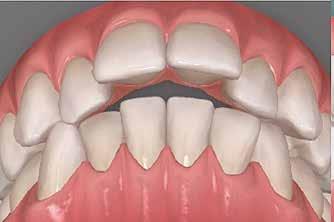

Lány páciensem I. fázisú kezelését 10 évesen kezdtük el bimaxilláris funkciós, kivehető készülékkel. Megfigyelhetőek a class 2-es eltérésnél tipikusan jellemző szűk felső és alsó fo-

gívek, valamint a nagy overjet, a mandibula disztál helyzete, továbbá a felső metszőfogak protrúziója, amelynek kialakulásához sokszor hozzájárul az ujjszopás is (1-3. képek)

A vegyes fogazati kezelési célok a fogívek tágítása és a mandibula meziális irányú növekedésének a biztosítása volt. Fontos, hogy az ilyen típusú készülékeket nem csak éjszaka, hanem napközben is – amennyit csak lehet – hordani kell a minél hatékonyabb működés érdekében. A 18 hónapos első fázisú kezelésnek köszönhetően az alap kezelési célok megvalósultak, sikerült a class 1-es okklúziót beállítani (4-7. képek).